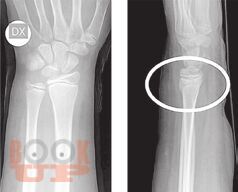

В книге рассмотрены вопросы применения методов визуализации при проведении судебно-медицинской экспертизы живых лиц и трупов. Особое внимание уделено судебно-медицинскому значению рентгенографии, посмертной компьютерной томографии и посмертной магнитно-резонансной томографии. Описаны возможности посмертной ангиографии для визуализации повреждений кровеносных сосудов. Авторы критически характеризуют преимущества и недостатки так называемой виртуальной аутопсии.